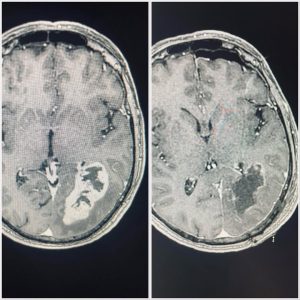

Gleolan is a visual imaging contrast agent that is used to help map out and define high-grade primary brain tumors like Glioblastoma for surgical removal. This exciting new method allows neurosurgeons to remove tumor cells more precisely, and more safely than ever before.

Surgical treatment of Glioblastoma can present a considerable challenge since the tumors often have “finger-like” projections that spread into different parts of the brain and can be hard to fully remove. Gleolan helps highlight these tumors in detail so that complete tumor removal can be more easily achieved.

Prior to surgery, patients drink the Gleolan contrasting agent which allows the surgical team to visualize the tumor in vivid contrast to distinguish it from the surrounding unaffected brain tissue. Under a special blue light microscope, the tumor turns bright pink or magenta—helping the surgeon to more safely and accurately remove all or most of the tumor from the brain.